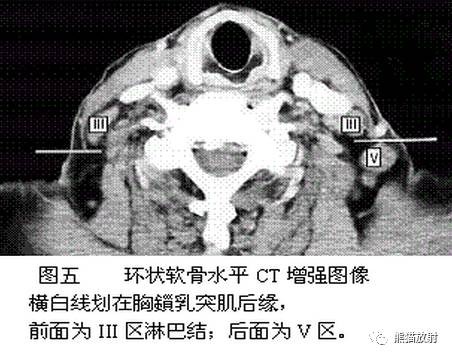

舌骨水平CT增强图像

横白线划在胸锁乳突肌后缘。

白线前为III区淋巴结,后为V区淋巴结。